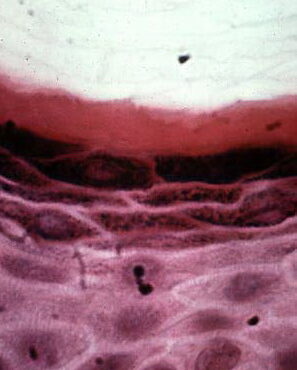

Dermoid_cyst =كيسة جلدانية Dermoid Cyst Dermoid cysts are subcutaneous cysts that usually are present at birth. They occur most commonly on the head, mainly around the eyes, and occasionally on the neck. When located on the head, they often are adherent to the periosteum. Usually they measure between 1 and 4 em in diameter. Histopathology. Dermoid […]